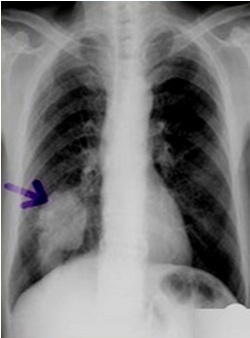

解题:箭头所指部分漆黑一片,根据公式得出气胸